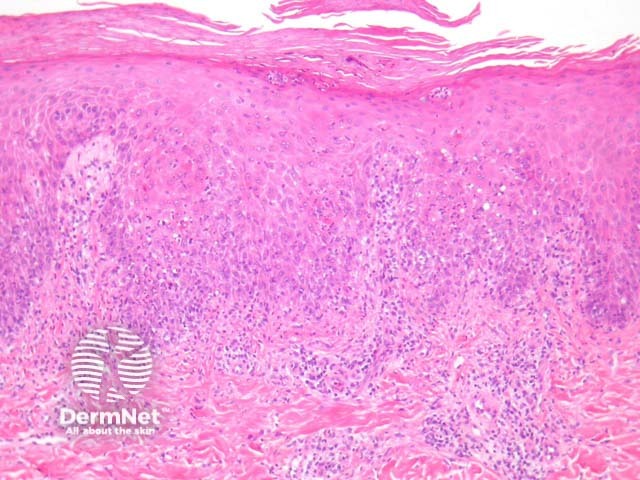

Secondary syphilis exhibits considerable histopathologic variability and may be easily misinterpreted. The epidermis is often involved and shows a psoriasiform hyperplasia with superficial neutrophils (figure 2). There is also a lichenoid tissue reaction, epidermal apoptosis and exocytosis of neutrophils (figure 3). The dermis shows a superficial and deep chronic infiltrate which may resemble the changes of primary syphilis. There are numerous plasma cells in about 1/3 of cases and often endothelial swelling (figure 1).

Figure 2